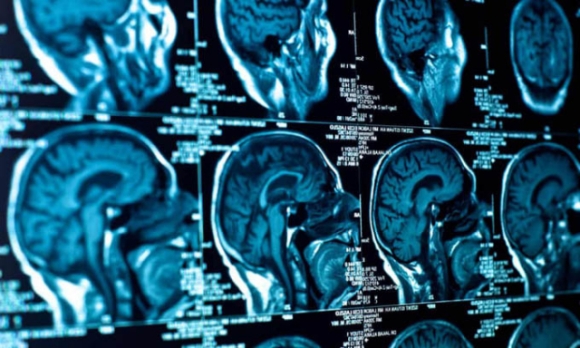

Trong một trường hợp khác, một bà mẹ trẻ nhanh chóng sụt gần 27 kg, bị sa sút trí tuệ và ảo giác. Ảnh chụp não cho thấy dấu hiệu tiến triển của chứng teo não.